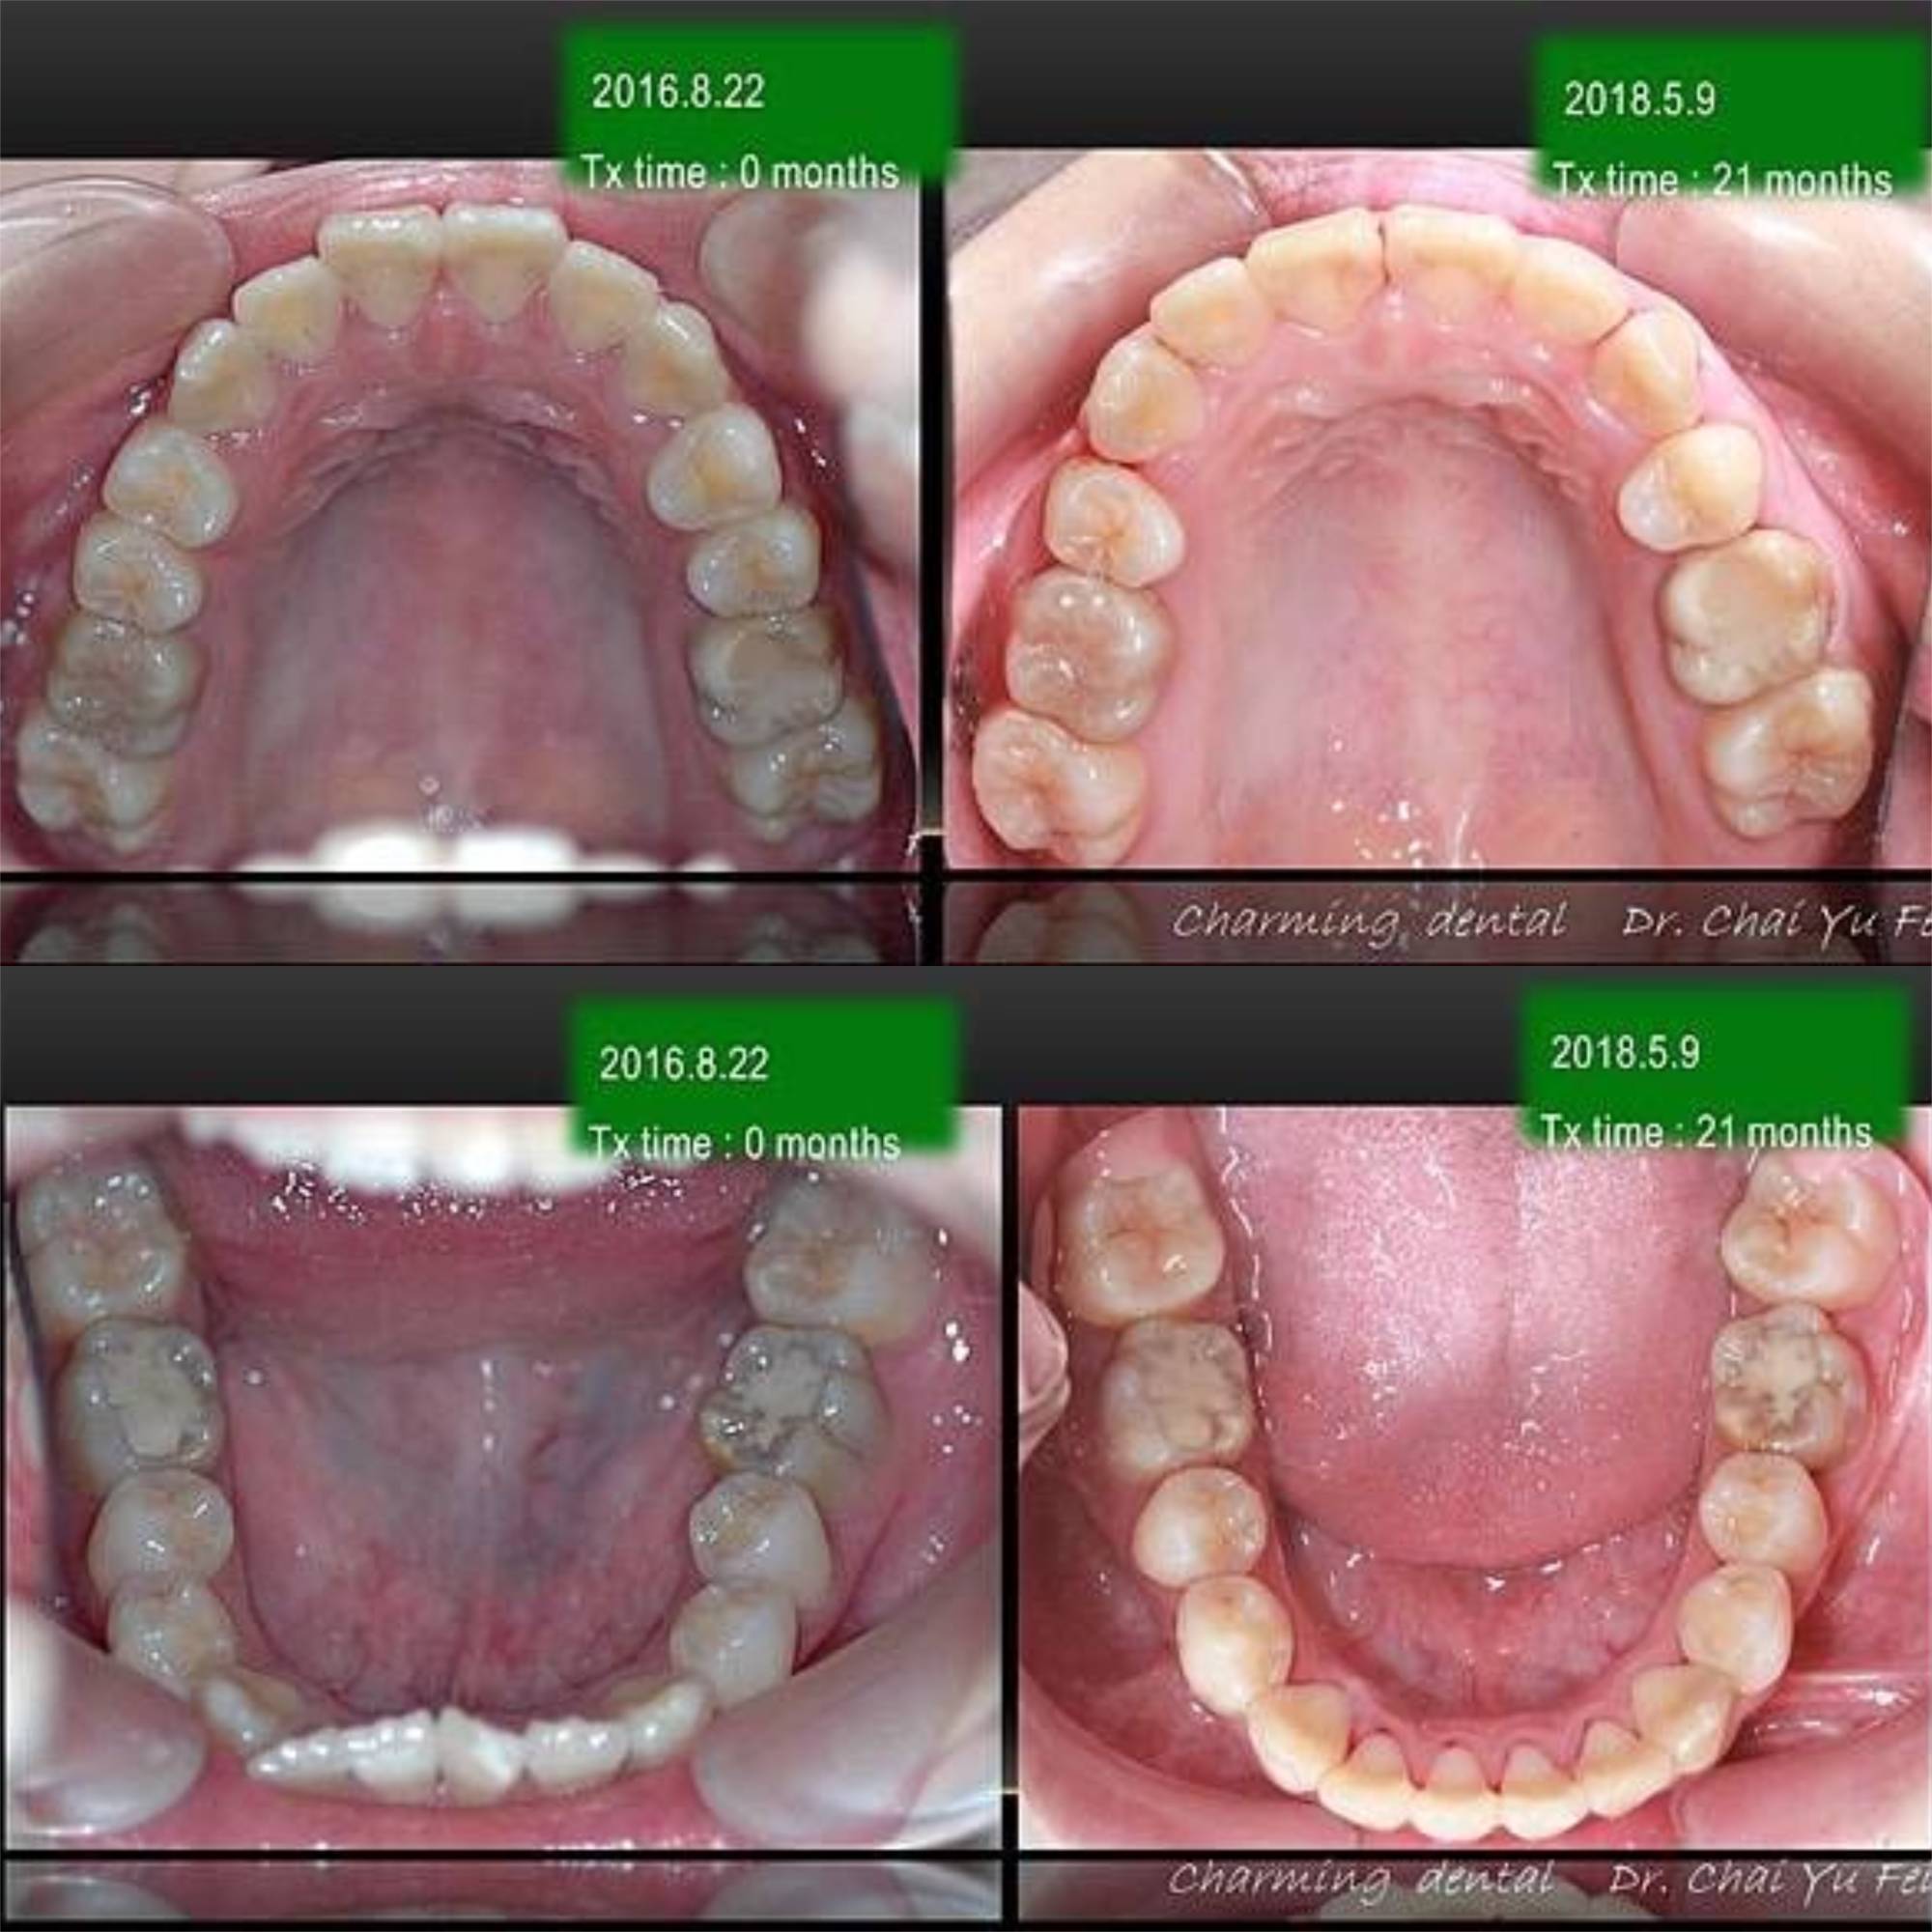

[ 治療時間 ] : 21 個月

[ 矯正器種類 ] : DR. TSENG 22X28 Slot 金屬零度矯正器

上顎兩顆小臼齒的拔牙空間順利關閉。

下顎咬合平面打平,藉由手術後退達到理想咬合。可以注意到她的右下第一小臼齒解剖構造比一般大!